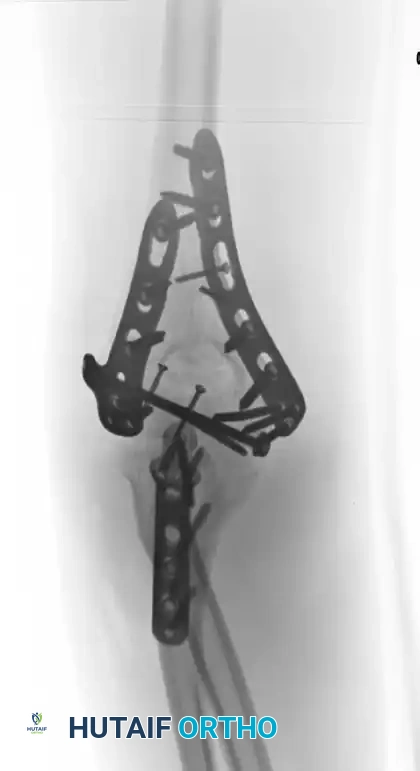

6. Bicolumnar Plate Fixation

Once the articular block is reconstructed and provisionally attached to the shaft, rigid bicolumnar plating is required. Plate the column with the better key to reduction first, followed by the opposite column.

There are two primary biomechanical constructs for bicolumnar plating:

1. Orthogonal (90-90) Plating: One plate is placed on the medial ridge, and the other is placed on the posterior aspect of the lateral column.

2. Parallel Plating: Plates are placed directly medially and laterally (180 degrees apart). Biomechanical studies (e.g., O'Driscoll's principles) suggest parallel plating may offer superior stability in axial compression, though both constructs are clinically acceptable if applied correctly.

Fixation 90-90

Fixation achieved with 90-90 locked plates through an olecranon osteotomy approach.